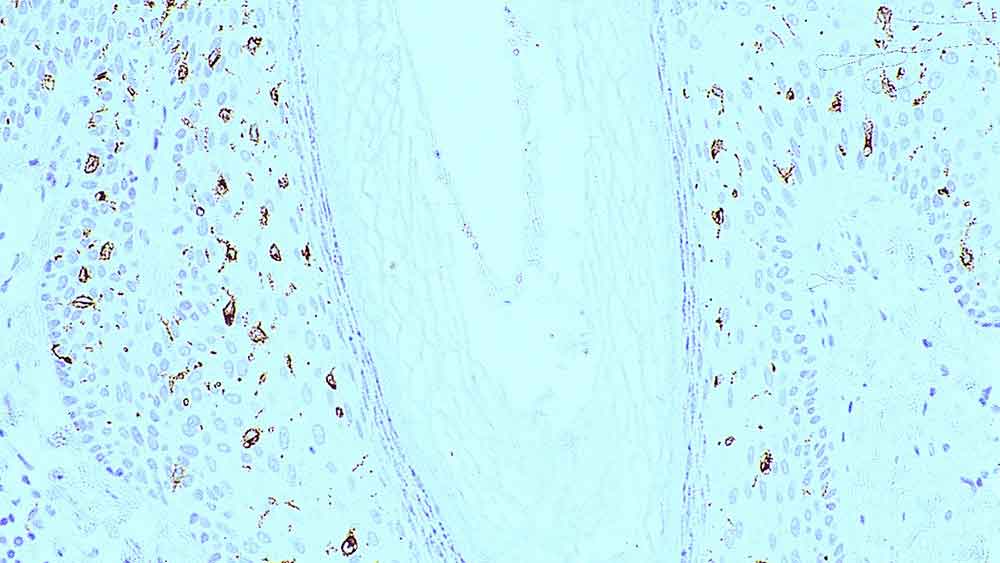

Human skin: immunohistochemical staining for langerin. Langerin: clone 12D6

Langerin is a type II transmembrane C-type lectin which has mannose-binding specificity. It is a 40 kD protein restricted to Langerhans cells that is involved in the internalization of cell surface material in these immature dendritic cells. Dendritic cells are antigen-presenting cells that are required for initiation of a specific T-cell-driven immune response. These cells are found in non-lymphoid tissue as immature cells whose primary function is to capture antigens through specialized surface membrane endocytic structures or through macropinocytosis. The dendritic cells migrate to secondary lymphoid tissue and mature into efficient antigen presenting cells. A part of the maturation process includes the loss of adhesion receptors such as E-cadherin and the disappearance of Birbeck granules. Although Langerin is reported to be located on the cell surface, it can be rapidly internalized following ligand capture into Birbeck granules. In fact, Langerin is a potent inducer of membrane superimposition and zippering leading to Birbeck granule formation. In reports it has been suggested that the induction of Birbeck granules is a consequence of the antigen-capture function of Langerin allowing passage into these organelles and providing access to a non-classical antigen processing pathway.

Langerin is recommended for the detection of specific antigens of interest in normal and neoplastic tissues, as an adjunct to conventional histopathology using non-immunologic histochemical stains.